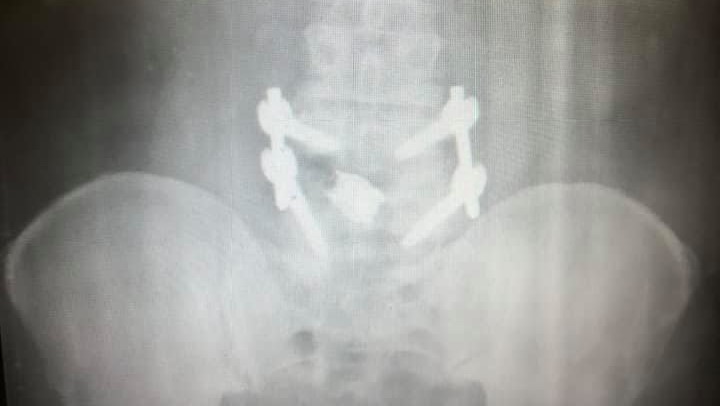

Hi All, my name is Kirsten and I live in Fort Wayne, Indiana. In early 2020 my dad John was riding his motorcycle in Key West, Florida where lives, and he went to stop and say hello to a friend he spotted but little did he know that a construction crew had left a 9" hole in the road partially uncovered exactly where he was about to put his foot down. This construction oversight caused him to lose balance and try to catch himself while his 700lb. touring bike to landed on top of him. He's undergone neck, back, knee, and elbow surgeries and still has more to go. Everything is also a bit more complicated for him because he lives on a boat by himself, aside from his best mate, his cat Mate.

I’ve been the helper most of my life! My life was flipped 180 with a motorcycle accident going zero mph and no one else involved. Had back, neck, left elbow n right knee. More needed ASAP but I’m tapped out.